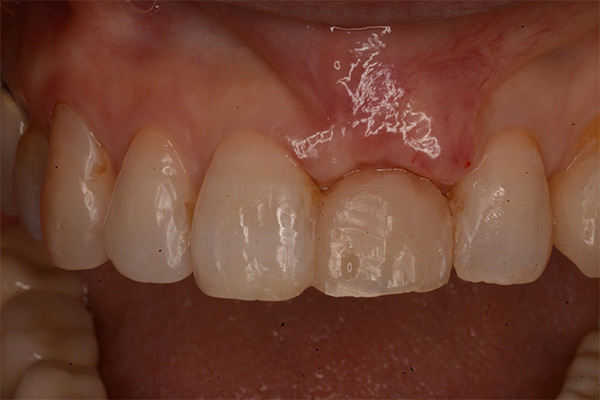

抜歯9ヶ月後(左)歯肉にヘコみができているので手術で歯肉を増大させる

2週間後、赤みは残るが歯肉の厚みは増えた(右)